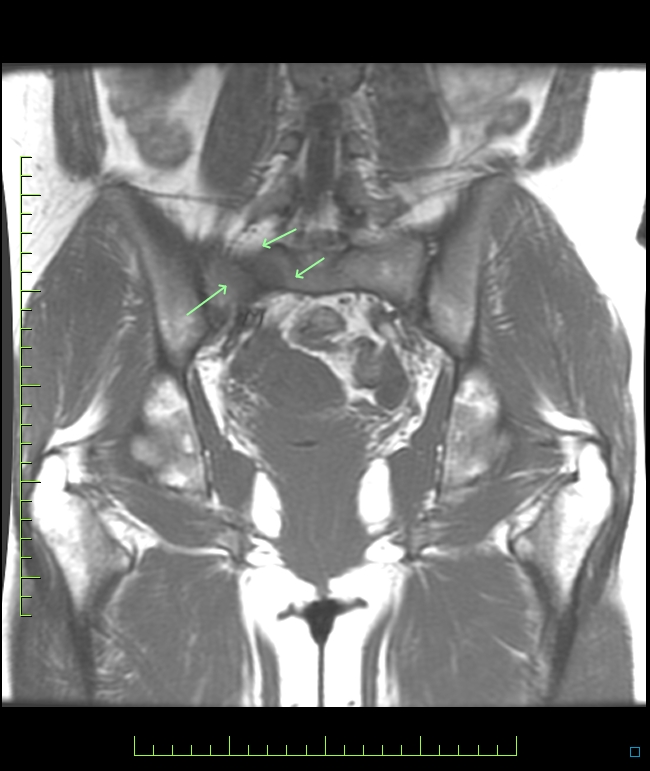

Remember all hip pain doesnt come from the hip. Not shown is edema in the sup pubic rami bilaterally as well.

Small FOV images of the hip only would have missed this.

Clyde and Nancys article attached: numerous case reports reported since Reference article.

R sacral stress fx